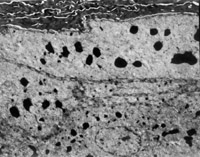

É˺ó12h¼±ÕïÈëÔº £¬£¬£¬ £¬£¬£¬£¬¼ì²éË«ÏÂ֫Ϊdz¢ó¶ÈÉÕÉË¡£¡£¡£¡£¡£´´Ãæ±íƤÒÑ»µËÀ°þÍÑ £¬£¬£¬ £¬£¬£¬£¬ÕæÆ¤²ã±äÐÔ»µËÀ³ÊÀ¯»ÆÉ«ºÍÀ¯°×É«Ïà¼ä£¨Í¼5-3-1£©¡£¡£¡£¡£¡£È¡¾Ö²¿×éÖ¯×ö²¡ÀíÇÐÆ¬¼ì²é £¬£¬£¬ £¬£¬£¬£¬ÏÔʾÉÏÆ¤×é֯ȫ²ã»µËÀ £¬£¬£¬ £¬£¬£¬£¬ÕæÆ¤²ã½ºÔ­ÏËά±äÐÔ £¬£¬£¬ £¬£¬£¬£¬½á¹¹ÔÓÂÒ £¬£¬£¬ £¬£¬£¬£¬Î¢Ñ­»·ðöÖÍ£¨Í¼5-3-2£©¡£¡£¡£¡£¡£

5-3-2 ÉÏÆ¤×é֯ȫ²ã»µËÀ £¬£¬£¬ £¬£¬£¬£¬½ºÔ­ÏËά±äÐÔ £¬£¬£¬ £¬£¬£¬£¬Î¢Ñ­»·ðöÖÍ HE¡Á20